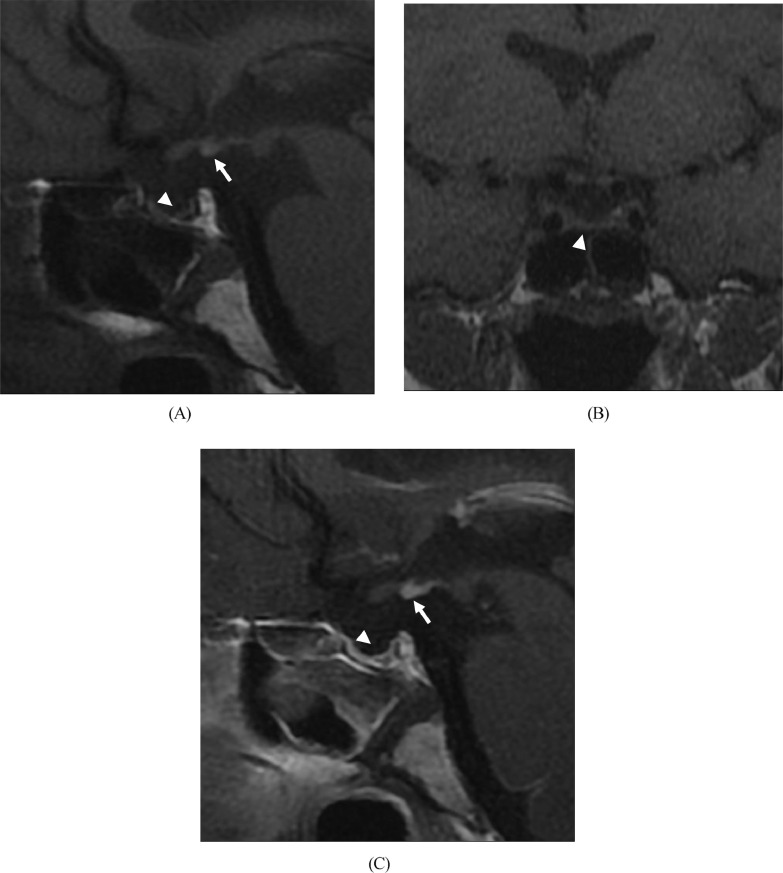

Brain MRI revealed an ectopic posterior pituitary lobe with no continuity of the pituitary stalk (Fig. 1). The patient had a history of pelvic delivery, and interruption of the pituitary stalk was presumed to be the causative lesion of hypopituitarism. A diagnosis of panhypopituitarism was made based on obstetric complications.

Fig. 1.

Panhypopituitarism in 38-year-old man presenting with delayed secondary sexual characteristics. Sagittal (A) and coronal T1-weighted magnetic resonance (MR) images (B) and contrast-enhanced sagittal T1-weighted MR image (C) at the time of initial evaluation. Sagittal (A) and coronal T1-weighted MR images (B) showing the pituitary stalk was absent and the pituitary gland (arrowhead) was very small and scarred. High signal (arrow) is seen in the median eminence, suggesting an ectopic posterior lobe. Contrast-enhanced T1-weighted images (C) showing ectopic posterior lobes (arrow) and pituitary gland (arrowhead).